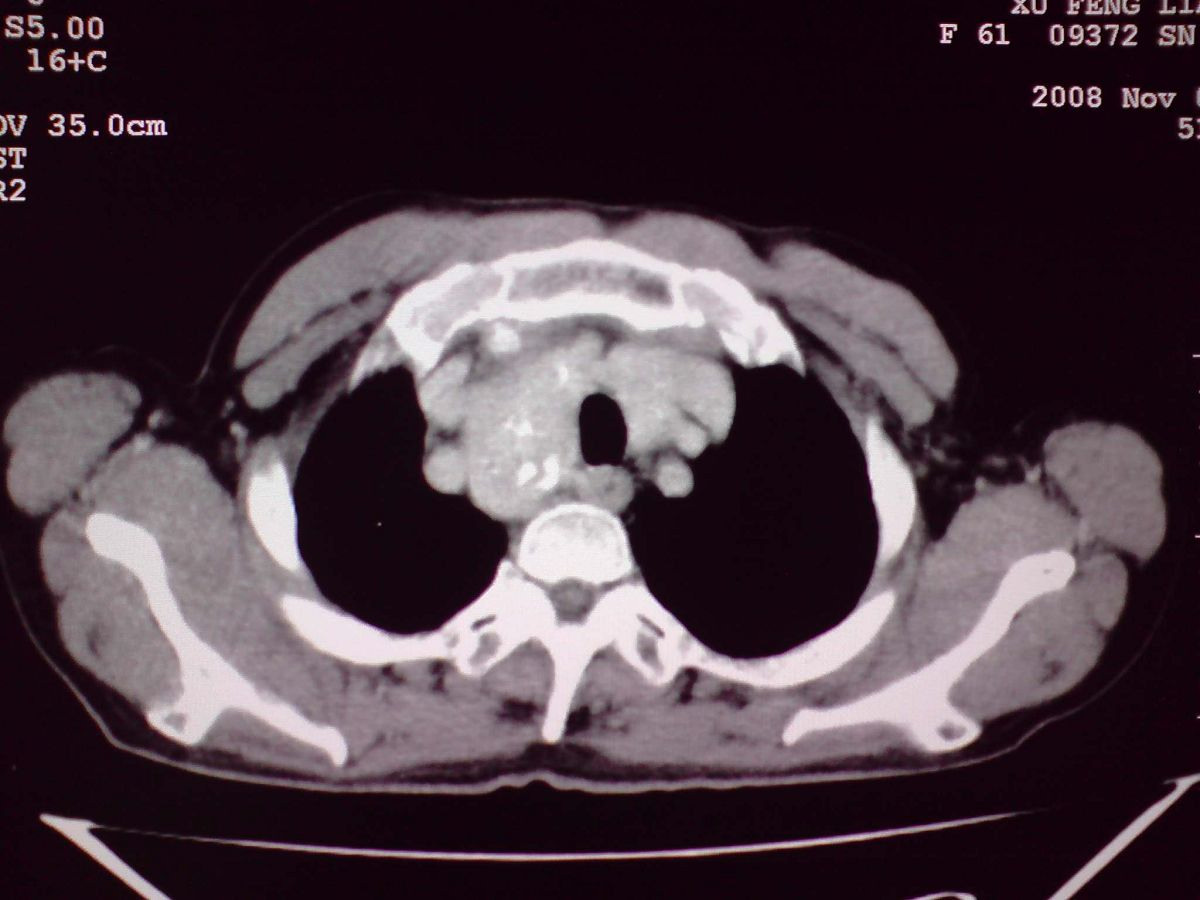

患者女性,65岁,无明显不适,甲状腺功能无异常

双侧甲状腺肿大,向下部分突入胸腔,双侧甲状腺内密度不均,可见结节状低密度影,并见散在斑点状钙化,增强后病灶实性部分强化明显,气管受压稍变窄左移。

考虑:双侧甲状腺腺瘤可能,不除外甲状腺癌。

甲状腺左右叶增大,并向下突入胸腔内,其内可见多发条片状钙化影及囊性低密度影,邻近组织及血管无浸润、包埋征像,双侧结节性甲状腺肿伴右侧甲状腺腺瘤形成可能性大,甲状腺癌待排;因病人就要手术,期待结果。